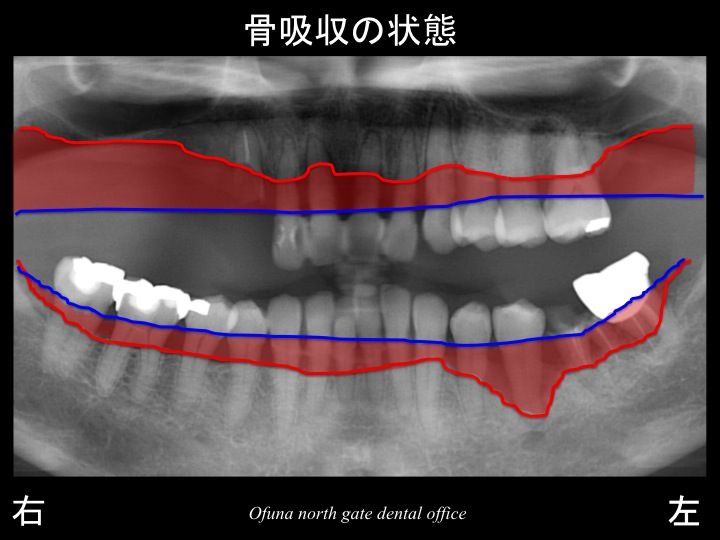

それでは、骨吸収の状態を見てみましょう!

いつものように 骨吸収の状態を分かりやすくするために

骨吸収の状態を線で書いたのが以下のレントゲンになります。

青線が骨吸収を起こす前の骨の位置です。

赤線は、現在の骨の位置です。

かなりの骨吸収が起こっているのが分かるかと思います。

さらに わかりやすくするために、

骨吸収部位を赤色で表示します。

歯周病により骨吸収が高度に起こっているのが分かるかと思います。